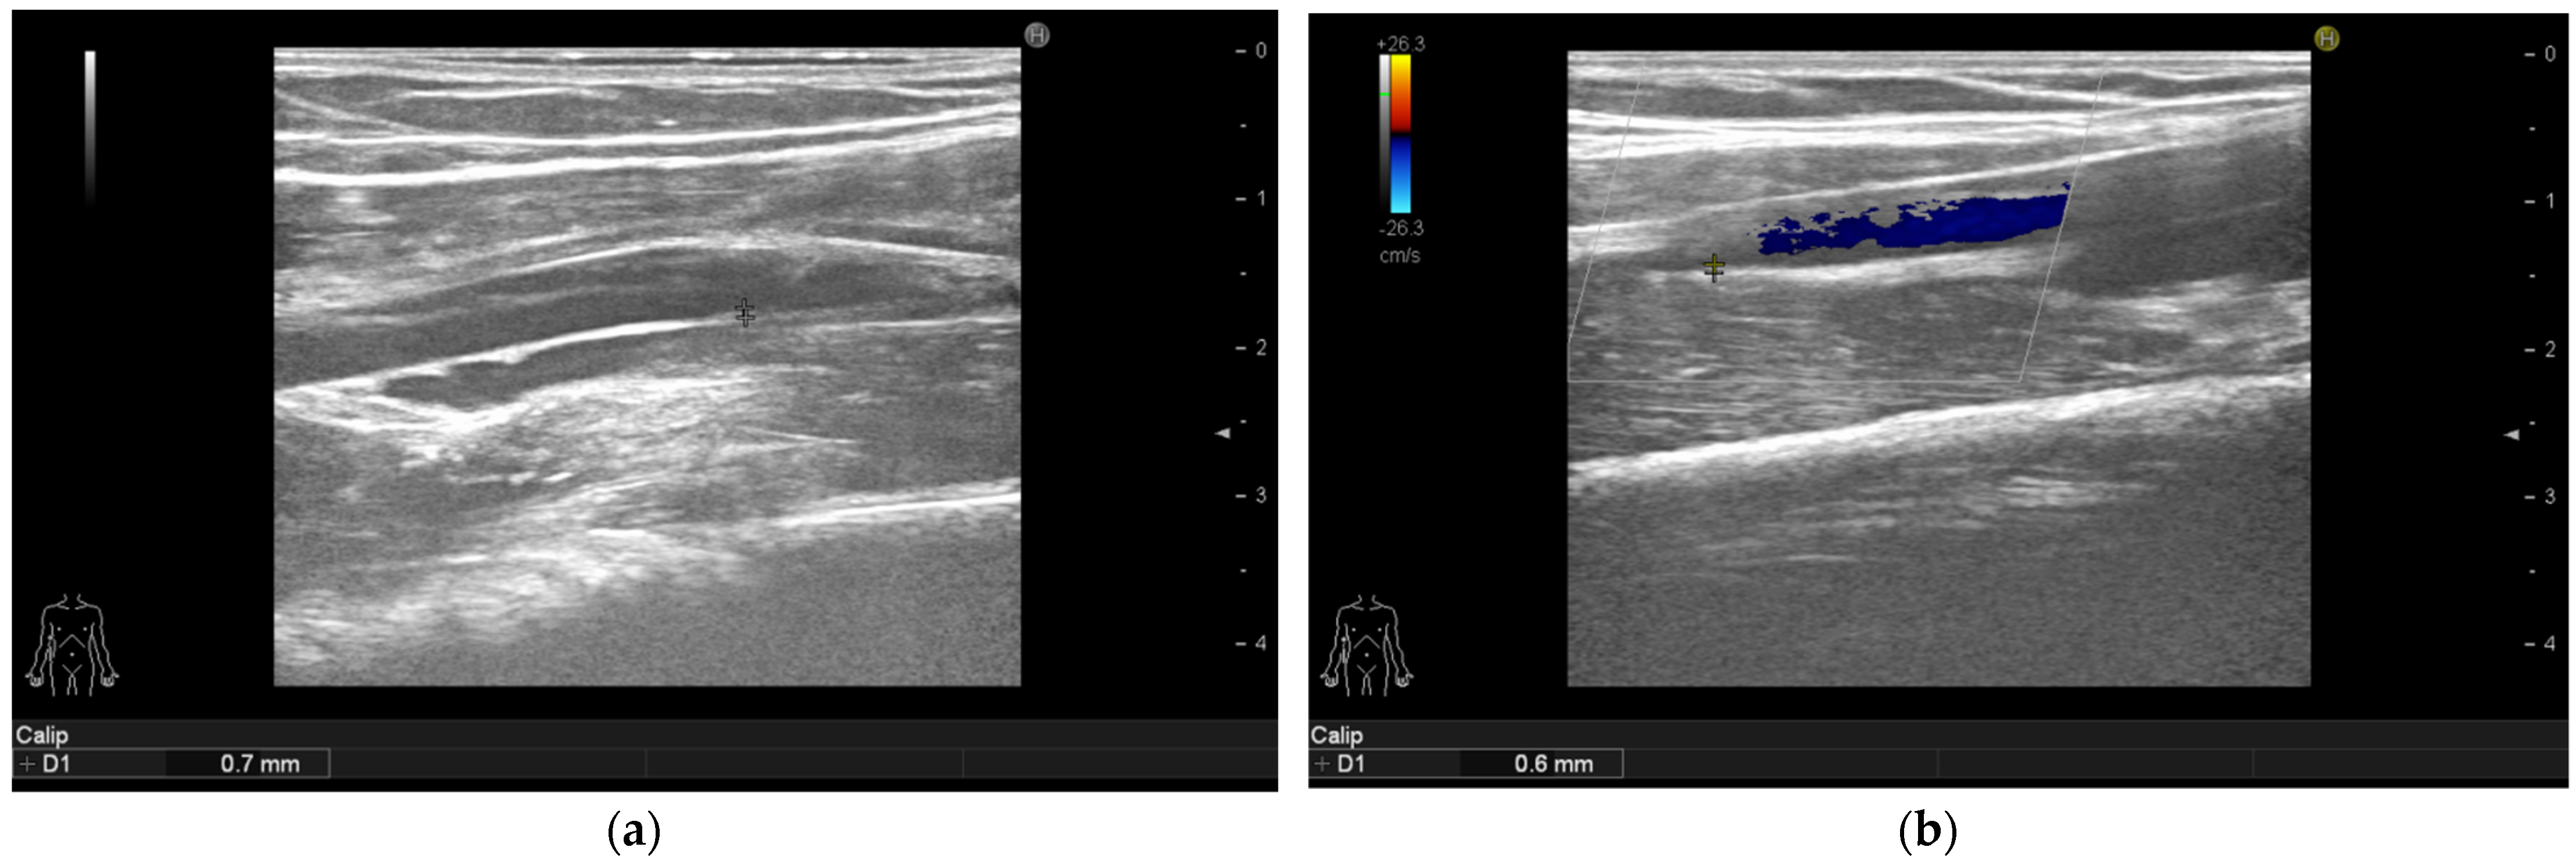

3.4. Ultrasonographic Findings

| Intima media thickness of the right brachial arteries (mm) | 0.75 (0.6–0.9) | 0.6 (0.5–0.7) | <0.001 |

| Intima media thickness of the left brachial arteries (mm) | 0.8 (0.6–0.9) | 0.5 (0.5–0.7) | <0.001 |